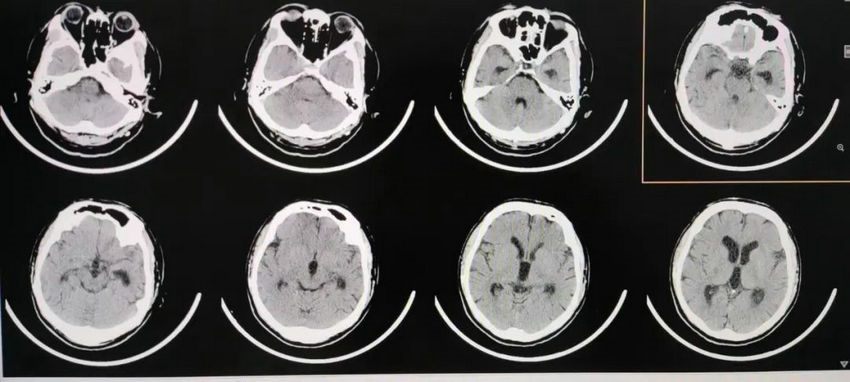

▲ 术后半个月头颅CT显示:侧脑室旁囊肿与侧脑室沟通,侧脑室旁囊肿大小及脑室大小变化不大